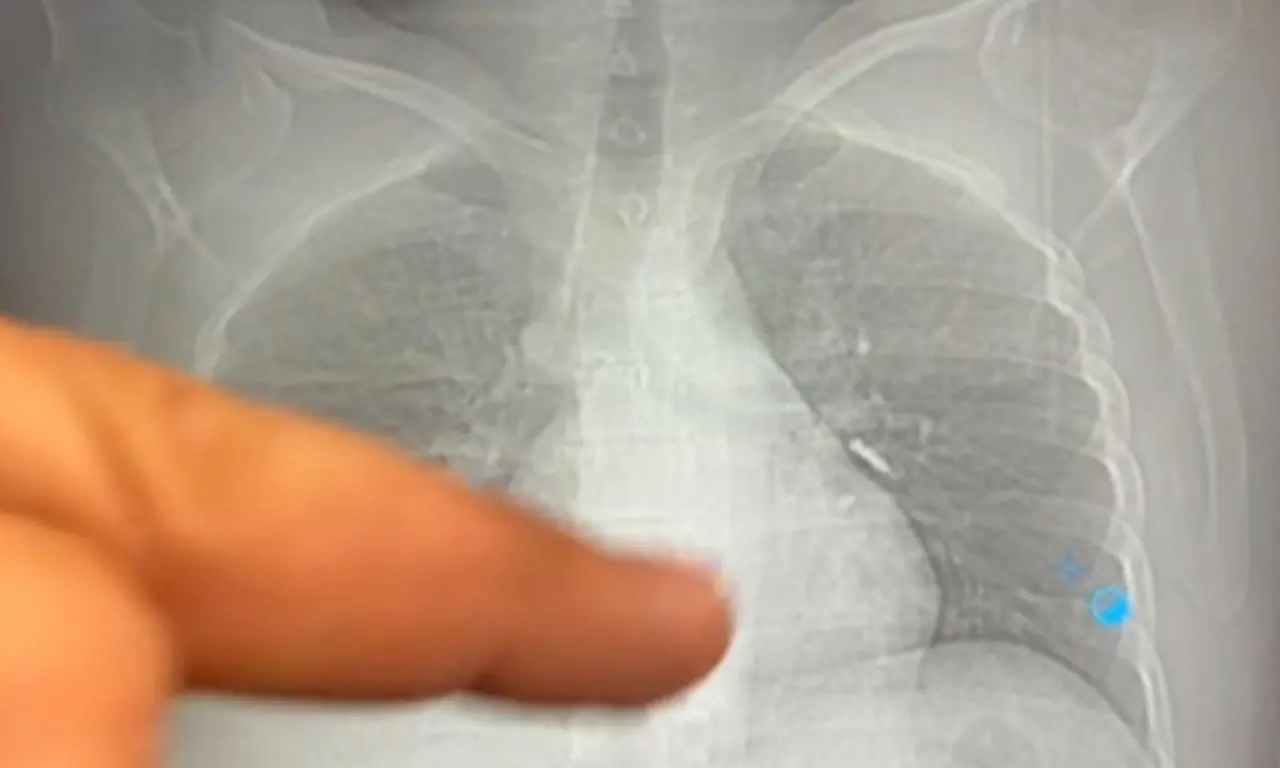

İmplant vidası, yapılan ilk kontrollerde hastanın sol akciğerinde, bronşların derin bir bölümüne saplanmış halde bulundu. Solunumu tamamen engellemeyen bu durum, yine de müdahale gerektirecek düzeyde tehlikeliydi.

Van Eğitim ve Araştırma Hastanesi’ne sevk edilen hasta, göğüs cerrahisi ekibinin gerçekleştirdiği uzun süren bronkoskopi müdahalesine alındı. Ancak vida yerinden oynatılsa da çıkarılamadı. Operasyonun ardından beklenmedik bir gelişme yaşandı: Hasta, geçirdiği şiddetli öksürükle birlikte implant vidasını midesine gönderdi. İlerleyen saatlerde, vida doğal yollarla vücuttan atıldı.

Göğüs Cerrahisi Uzmanı Op. Dr. Sadullah Aksoy, dişe özel vida yapısının bronşlardaki küçük damarlara saplanması nedeniyle işlemin oldukça zorlu geçtiğini belirtti.